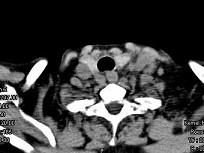

问题 女,69岁,低热、乏力三月余,消瘦,食欲不佳,PE:腹股沟触及多个肿大的淋巴结,质较硬,尚可移动,CT如图所示,最可能诊断为()

选项 A.淋巴瘤 B.颈淋巴结结核 C.颈淋巴结结核 D.结节病 E.淋巴结炎

答案 A